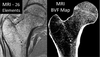

• the NYU MRI protocol was tested on first study subjects 08/08/24 on a Siemens 3T MRI Vida installed and operating at Richmond VAMC since Summer 2023; the NYU Co-I Chang and UPenn Co-I Rajapakse confirmed the high quality of images acquired for the hip (proximal femur) and ankle (tibia) of the first subject. Recruitment of SCI study subjects anticipated for quarter 1 of calendar year 2025.

Methods: Use off-the-shelf equipment (coils) and an MRI method, previously used to study microarchitectural changes with steroid-induced bone loss, to evaluate individuals with SCI (from a pool of 800 veterans with SCI served by McGuire VA Medical Center) to verify the detection of disruptions to microarchitecture with skeletal unloading. Able-bodied military personnel will serve as controls to determine if the SCI disuse condition can be used as a ground-based analog of LD spaceflight to correlate spaceflight duration with changes in hip microarchitecture.